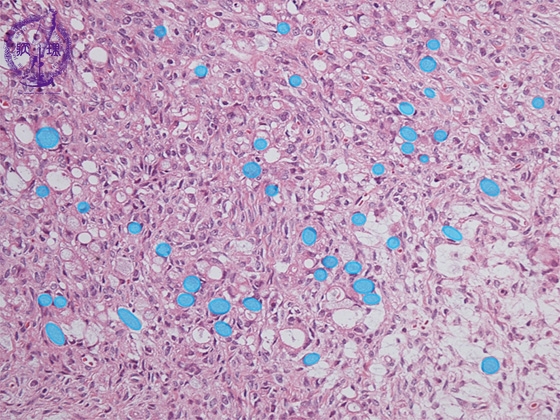

- ★(12)Krukenberg tumor

Histology (HE stain, low power): Signet-ring cell carcinoma proliferated with scattering pattern (light blue). Fibroblasts demonstrated reactive proliferation in interstitium.